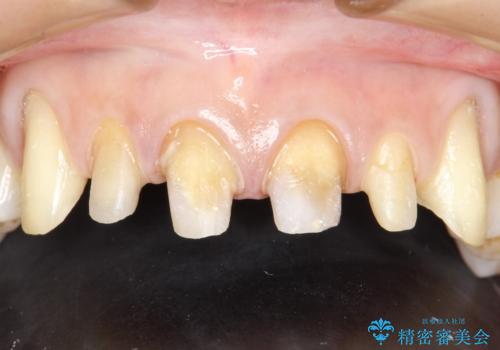

- 昔装着した前歯のかぶせ物を新しくしたいとのことで来院されました。

ご自身の歯とかぶせ物の境目が露出しておりました。

また犬歯の形も気になるとのことでした。